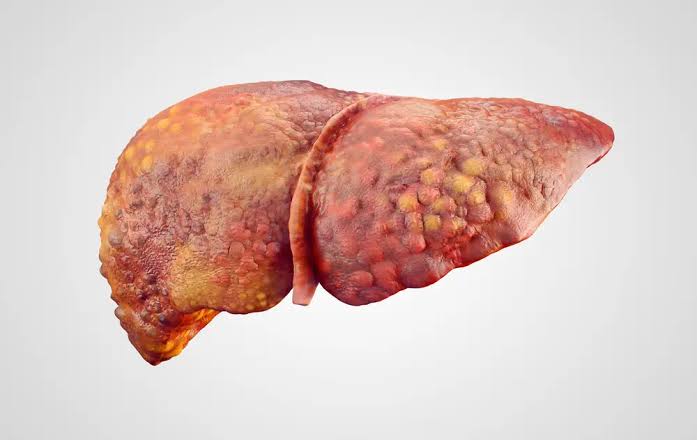

Child-Pugh Təsnifatı